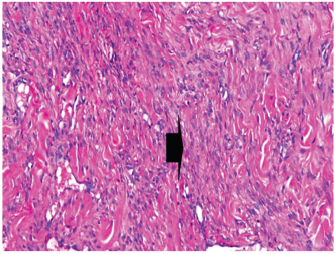

At 7 days post wounding; the inflammatory reaction was moderate and characterized by polymorphonuclear cells and macrophages infiltration with the presence of small scab covering the wound surface. Early evidence of epithelization was detected and represented by the proliferation of epidermal epithelium under the scab. There was marked thickening and hyperplastic proliferation of epidermal epithelium at the free wound edge (Fig. 6). The dermal tissue underlying the wound area showed few polymorphonuclear cells infiltration and more abundant mononuclear cells. Fibroplasia and angiogenesis were detected in the dermis and more extensive in deeper areas of the dermis which characterized by fibroblast and angioblast proliferation forming immature young granulation tissue (Fig. 7). At 14 days post wounding, the wound area was covered by a complete layer of epidermal epithelium indicating a good epithelization rate of the wound. Proliferation of cutaneous appendages was detected. The newly formed epithelium was thick and showed partial keratinization and epithelial differentiated stratum containing polyhedral keratinocyte with the appearance of keratohyalin granules in their cytoplasm (Fig. 8). The dermal tissue showed deposition of parallel well organized and interconnected collagen bundles that arranged parallel to epidermis associated with enhanced angiogenesis represented by well-developed blood capillaries (Fig. 9). At 21 days post wounding, remodeling of the formed epithelium with relatively small scar formation and mild restoration of skin appendages. Keratinized and differentiated stratum comprising the covering epithelium and the newly formed skin appendages from the basal epidermal epithelium were detected (Fig. 10). The dermal tissue revealed well-formed organized tissue consisted of parallel compact and interconnected bundles of collagen with scant angiogenesis (Fig. 11). At 28 days post wounding, well-formed scar tissue covering highly cellular organized tissue was detected (Fig. 12). The dermal tissue revealed well-arranged compact collagen bundles containing scarce blood vessels (Fig. 13).

Fig. 8. Skin of a goat from electroacupuncture group at 14 days post wounding showing enhanced reepithelization evidenced by differentiated polyhedral keratinocytes in the stratum spinosum and keratohyalin granules in the stratum granulosum (arrow) and keratinization (arrow head), (HE ×100).

Fig. 9. Skin of a goat from electroacupuncture group at 14 days post wounding showing well organized and interconnected collagen bundles that arranged parallel to each other and to epidermis (arrow head) associated with enhanced angiogenesis represented by well-developed blood capillaries (arrow), (HE ×200).